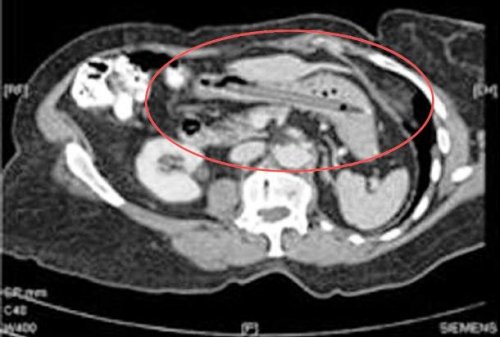

Бутерброды с бананом, картошка фри с молочным коктейлем, соленья с арахисовым маслом... У некоторых людей есть необычные привычки питания и предпочтения в еде. Однако после прочтения этой статьи вы сочтёте эти маленькие отклонения абсолютно приемлемыми. Ознакомьтесь с этими странными предметами, которые были найдены в человеческом кишечнике (которые, вероятно, заставили поёжиться даже самых опытных хирургов). 25. Бутылка Мужчина обратился в китайскую больницу с жалобами на боли в животе. То, что врачи обнаружили, было шокирующим и довольно смущающим для бедолаги. Оказалось, причиной брюшной боли была бутылка, которую удалили хирургическим путём. 24. Столовые приборы Маргарет Далман (Margaret Daalman) из Нидерландов попала в больницу с болями в желудке. Хирурги в Роттердамской больнице отправили её на рентген и были потрясены, когда изображение показало 78 различных предметов столовых приборов в желудке 52-летней женщины. К счастью, она ела только ложки и вилки, а не ножи. 23. Батарейки Каждый год регистрируется несколько случаев, когда дети съедают батарейки. К примеру, в декабре 2013 года 13-месячный мальчик из города Лестер (Leicester), Англия, умер от внутреннего кровотечения после проглатывания батарейки, которую он нашёл в своём детском саду. 22. Живые лягушки Янг Дингкай (Yang Dingcai) с юго-востока Китая говорит, что 40-летняя привычка глотания живых лягушек и крыс помогла ему избежать проблем с кишечником и сделала его сильным. 21. Гвоздь Китайский плотник Ли Сянъян (Li Xiangyang) держал гвоздь между своих зубов, когда он вдруг закашлялся и проглотил его. Он был доставлен в больницу, где врачи сделали рентгеновский снимок и нашли гвоздь в правом лёгком. Профессор Ху Кэ (Hu Ke) попытался удалить его с помощью бронхоскопа через его горло. Однако в тот момент, когда он был уже на грани того, чтобы вытянуть гвоздь, Ли снова закашлялся и всосал его обратно. На этот раз гвоздь оказался в его левом лёгком. Ху попытался снова, но в последнюю минуту, Ли невольно сглотнул и гвоздь снова исчез. В конце концов, врачи обнаружили гвоздь и, наконец, смогли удалить его с помощью гастроскопического зажима. 20. Ручная граната Рентген выявил ручную гранату в желудке террориста. Очевидно, он не продумал свой план достаточно хорошо, потому что у него не было возможности на самом деле детонировать гранату. 19. Ложка 33-летняя женщина пыталась ложкой удалить рыбную кость, попавшую в её гортань. Она случайно проглотила ложку, и её пришлось отвезти прямиком в операционную, чтобы удалить ложку хирургическим путём. 18. Пуля Четырёхлетняя девочка из города Тхане (Thane), Индия, проглотила пулю в районе Локманья Нагар (Lokmanya Nagar). Девочка играла в окрестности, когда она нашла пулю, лежавшую на земле. Предположив, что это был шоколад, она взяла её и положила в рот. Девочку отвезли в больницу, где врачам удалось успешно вытащить свинец без хирургического вмешательства. 17. Наркотики Нигерийца, пойманного в Международном аэропорту Куала-Лумпур (Kuala Lumpur International Airport) в Малайзии, доставили в больницу, где рентген показал наличие инородного предмета в его желудке. Предметом, как оказалось позднее, были 54 капсулы метамфетамина. 16. Живой угорь Мужчина из Китая обратился в больницу после того, как по сообщениям, в нём застрял живой угорь. Мужчина вставил 50-сантиметрового азиатского рисового угря себе в анус, увидев, как это сделали в порно. Поэтому ему пришлось выдержать операцию, которая длилась всю ночь, чтобы извлечь этого угря. Как сообщается, члены команды врачей сказали, что угорь, который «просто пытался найти выход», был жив, когда его вытащили, но вскоре скончался. 15. Обручальное кольцо Кейтлин Уиппл (Kaitlin Whipple) проглотила обручальное кольцо, которое её бойфренд Рид Харрис (Reed Harris) поставил в её мороженое. После того, как Кейтлин проглотила его, она с недоверием отнеслась к заверениям своего приятеля о том, что он поставил кольцо в её мороженое. Риду пришлось отвезти её на рентген, чтобы это доказать. 14. Ножницы 27-летний Конг Лин (Kong Lin) использовал 10 сантиметровую пару маникюрных ножниц в качестве зубочистки после еды. Однако когда один из его друзей рассказал анекдот, Конг рассмеялся и быстро проглотил ножницы. 13. Самолёт Мишель Лотито (Michel Lotito) являлся французским конферансье, известным как человек, который мог съесть несъедобное. Он также был известен как «Месьё Съешьвсё» (Monsieur Mangetout). Во время своего представления Лотито поглощал металл, стекло, резину и другие материалы от таких предметов, как велосипеды, телевизоры, или даже самолёт (Cessna 150, если быть точным). Съедение самолёта заняло у него около двух лет. Лотито не часто страдал от вредных последствий из-за своей диеты, даже несмотря на то, что он ел материалы, которые, как правило, считаются ядовитыми. Он, видимо, обладал желудком и кишечником, чьи стенки были двойной толщины, и его пищеварительные кислоты предположительно были необычайно мощными. 12. Мобильный телефон На этом удивительном рентгеновском снимке, сделанном в тюрьме в Сан-Сальвадор (San Salvador) видно, насколько далеко могут зайти люди, чтобы не потерять связь. 11. Монеты 62-летний мужчина с историей психиатрических проблем, отправился в отделение неотложной помощи в 2002 году, мучаясь от болей в животе. Врачи были шокированы, когда они обнаружили причину боли пациента - в его животе было приблизительно 350 монет (на общую сумму в 650 долларов) наряду с различными ожерельями и иглами. Всё это было настолько тяжёлым, что его живот провис между его бёдер. 10. Ручка 76-летняя женщина посетила гастроэнтеролога из-за желудочных проблем, связанных, в том числе с потерей веса и диареей. Рентген показал ручку, застрявшую в желудке женщины. После того, как ручка была извлечена из кишечника, где она находилась в течение 24 лет, оказалось, что она всё ещё была в рабочем состоянии. 9. Пружины от кровати Рентгеновские снимки из центральной тюрьмы в городе Роли (Raleigh), штат Северная Каролина, показали такие предметы, как пружины от кровати, которые заключённые глотали, чтобы получить возможность поездки в больницу, расположенную на воле. 8. Человеческий плод Санджу Бхагат (Sanju Bhagat) из Индии постоянно являлся предметом насмешек из-за своего чрезмерно большого живота. Однажды ночью его доставили в больницу из-за одышки и сильной боли. Когда доктора попытались удалить то, что, как они думали, было опухолью, они были шокированы, увидев частично сформировавшийся человеческий плод. 7. Ключ 18-летний студент компьютерного дизайна проглотил 5-сантиметровый ключ на вечеринке, чтобы помешать своим друзьям отвезти его домой, после того как они решили, что он уже достаточно выпил. Врачи отправили его домой, сказав ему, чтобы он позволил природе сделать своё дело, и ключ появился 31 час спустя. 6. Крупная галька В 2006 году девушка из Фошань (Foshan), Китай, проглотила более 20 камней гальки в минуту гнева после большой ссоры со своим бойфрендом. Изначально, она думала, что камни выйдут сами по себе но, к сожалению, они этого не сделали и оставались в её теле в течение следующих нескольких дней. 5. Магниты Когда 8-летняя ученица Хэйли Ленц (Haley Lents) из города Хантингбург (Huntingburg), штат Индиана, нашла блестящие металлические предметы, разбросанные по дому она, естественно, предположила, что они были конфетами. Вскоре её кишечник был заполнен магнитами, и её пришлось доставить в больницу, чтобы помешать их скреплению внутри её кишечника. 4. Электрическая лампочка Когда врачи в Пакистане удалили лампочку из толстого кишечника заключённого, у него не было никакого объяснения для этой крайне необычной находки, и он казался настолько же ошарашенным, как и все остальные. 3. Хирургический пинцет 57-летний Дариуш Мазарей (Daryoush Mazarei) испытывал сильную боль после обширной операции. Несмотря на хронический дискомфорт и боль, Мазарею неоднократно говорили, что с ним всё в порядке в физическом плане. Когда врачи Мазарея наконец сделали ему компьютерную томографию, они увидели большой инородный предмет, находившийся в его животе. После повторного открытия брюшной полости пациента, хирурги нашли пару медицинских пинцетов, которые были случайно оставлены внутри мужчины во время последней операции. 2. Комок волос Неизвестная 18-летняя женщина из Новой Англии, США, попала в больницу с болями в желудке и потерей веса. В животе врачи обнаружили огромный комок волос, который занимал почти весь её живот. Пациентка сказала, что у нее есть привычка кушать собственные волосы. Ей пришлось перенести традиционную операцию, чтобы убедиться в том, что весь комок шерсти был удалён. 1. Вилка 40-летний Ли Гарднер (Lee Gardner), случайно проглотил вилку длиной в 22 сантиметра. Врачи сказали ему, что вилка быстро пройдёт по организму, но это оказалось не так. Спустя 10 лет он начал рвать кровью и страдать от ужасных спазмов желудка. Он перенёс операцию, чтобы удалить вилку в Барнсли, Англия и полностью выздоровел. |